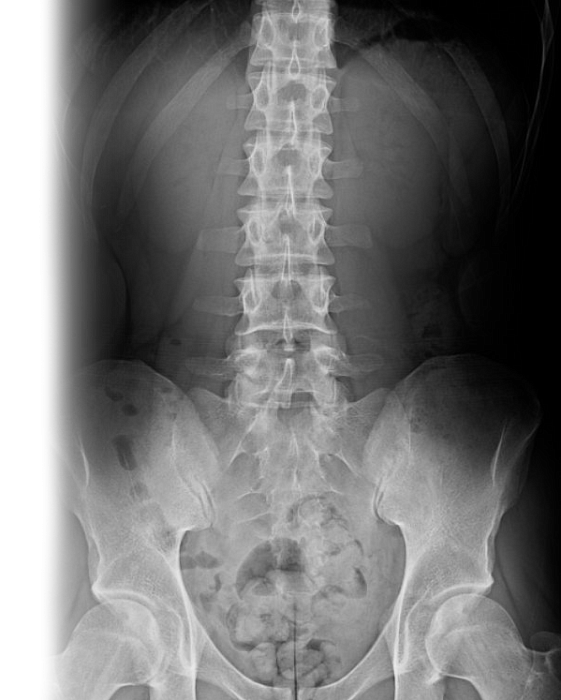

Рентгенография пояснично-крестцового отдела позвоночника Рентгенография пояснично-крестцового отдела позвоночника

Рентгенография пояснично-крестцового отдела позвоночника

Рентгенография пояснично-крестцового отдела позвоночника – важный метод скринингового исследования, который позволяет оценить состояние пояснично-крестцового отдела позвоночника.

Диагностическая услуга выполняется в двух проекциях.